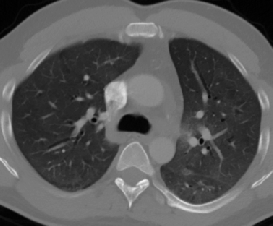

Some examples of CT slices from the cluster centers are given below. Figure 4 shows 10 consecutive slices from COVID-19 cluster center 0. Medical experts have annotated it as ’bilateral ground glass regions that appear, especially in lower lung lobes’. Figure 5 shows 10 slices from COVID-19 cluster center 2. According to medical experts’ annotation, this is consistent with ’COVID-19 pneumonia bilateral thickening filtrates’. Figure 6, on the contrary, shows 10 slices from non COVID-19 cluster center 9.